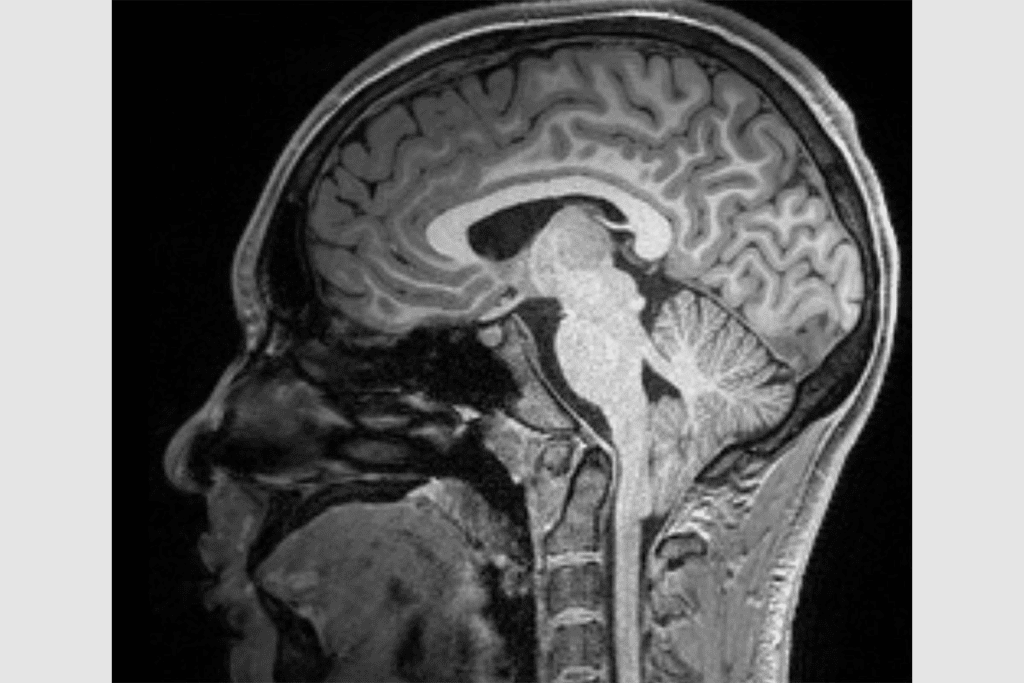

Magnetic Resonance Imaging (MRI) is key in finding Chiari malformation. It shows us the cerebellum and brainstem clearly. This helps us see how bad the malformation is.

We use high-detail MRI scans to see how far the cerebellum is moved. We also look for other problems like syringomyelia or tethered cord syndrome.